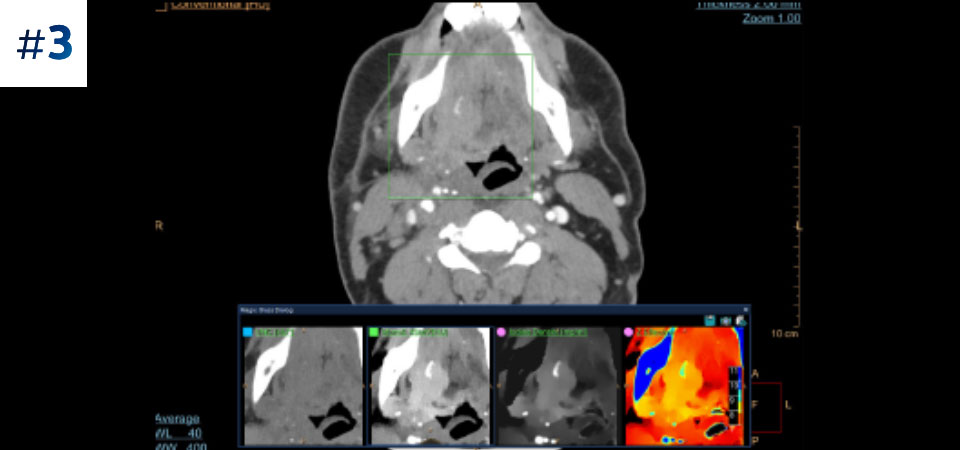

Neck mass

With detector-based spectral, you acquire multiple layers of data—conventional and spectral—within a single exposure and without special scan modes for improved tissue characterization and visualization.

Always available 100% spectral, 100% of the time for results that are always available on-demand, even retrospectively.

Reduced follow-up exams Improved tissue characterization and visualization may reduce the need for follow-up scanning for sub-optimal exams and incidental findings.